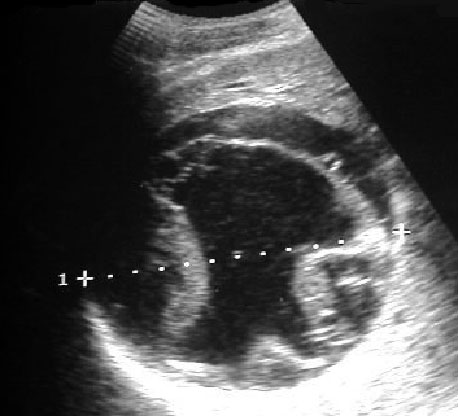

Signo de quiste hidatídico en el que se ha producido el colapso de las membranas parasitarias. Corresponde a una imagen lineal separada de la pared del quiste y plegada, visible tanto en ecografía como en TC y en resonancia.

Imagen de ecografía del mismo quiste hidatídico.